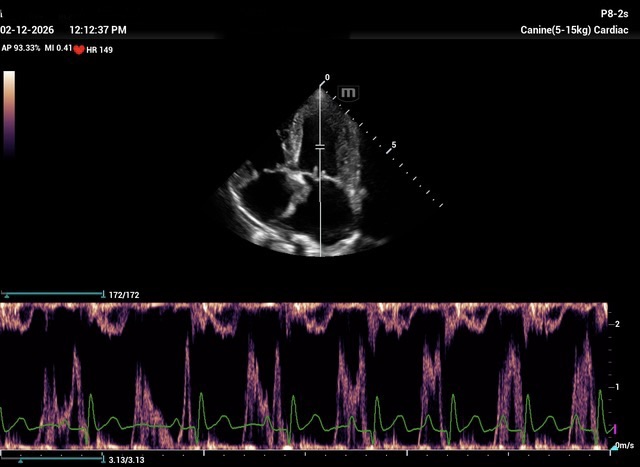

How would you diff b/w reverse remodelling and MV stenosis. Presented at recheck with mod severe pulmonary HT. Smll dog treated for chronic MVD stage C. US= LV under loading, FS > 50%, LAE remains significant. M e-vel is consistently 1.5m/s or higher but dec. time and press half time appear normal. E:A ratio around 1. Would LAE remain with aggressive medical Tx for MVD due to LA remodelling, LA compliance ,chronicity of MVD and ongoing reg. vol. compared to potential for LV to undergo reverse remodelling with Tx. Is stenosis seen much in min breed old dogs? Ls7 vid=2024. Tks!!

I see MS at all ages, because it is frequently missed in young dogs. But this case is not a MS. It is diagnosed as a combination of 2D-echo findings and the typical Minflow profile (E-wave very high frequently >2 m/s) confluent with A-wave. See image and video.